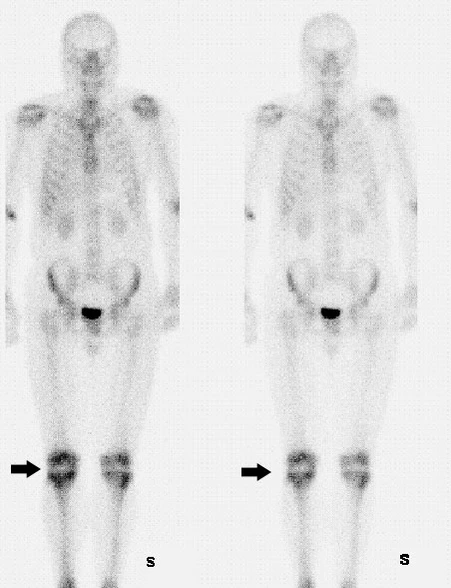

При остеосцинтиграфии в неизменённых костных структурах скелета накопление 99mTc-золедроновой кислоты, как и других остеотропных РФП симметрично. При использовании режима исследования «whole body» (планарная сцинтиграфия всего тела в двух проекциях: передней и задней) в передней проекции относительно более выраженная степень накопления РФП встречается в суставах, метафизах длинных трубчатых костей, в грудине, костях лицевого черепа, гребешках подвздошной кости. В задней проекции — в тазовых костях, лопатках, крестце и позвоночнике.

Остеосцинтиграфия — превосходный метод обнаружения скрытых, стрессовых переломов (которые встречаются у 10 % бегунов), микротрещин, ушиба кости и спортивных травм. Для диагностики травмы также возможно применение метода трёхфазной сцинтиграфии[7].